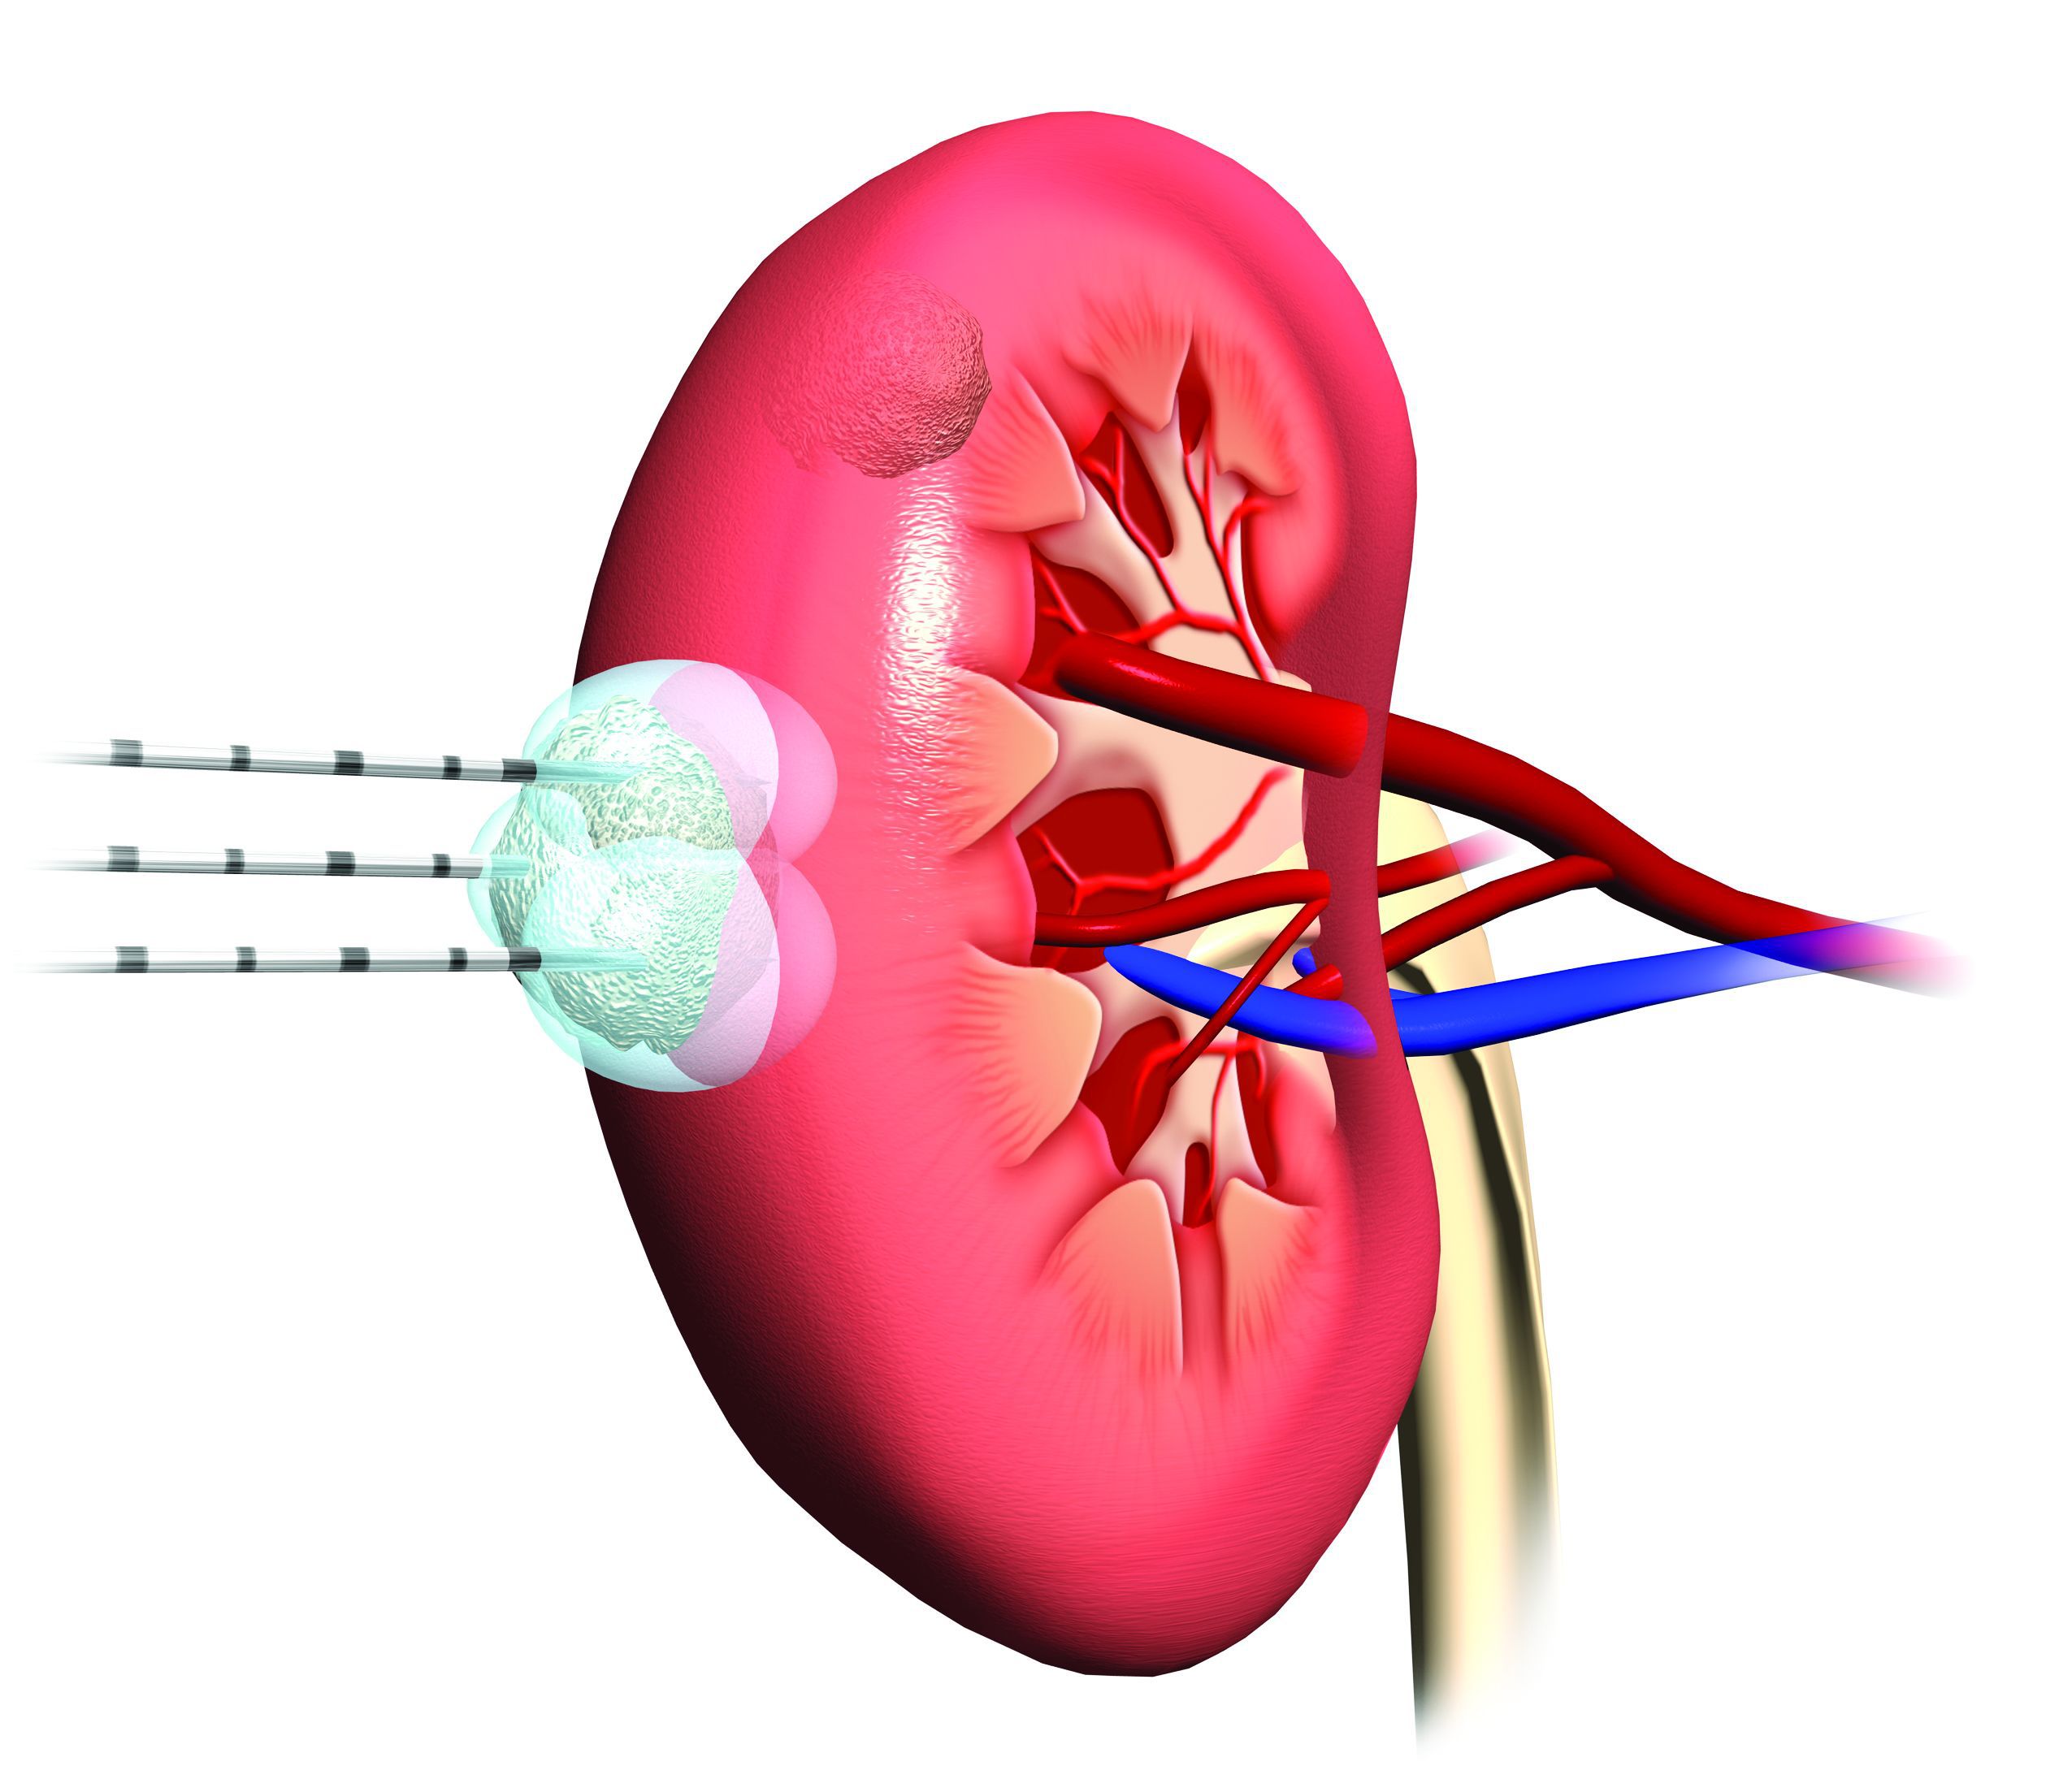

Called cryoablation therapy, the procedure uses very thin needles inserted into the kidney through the skin to deliver the therapy directly to the site of the tumor. Argon gas is circulated through closed metal needles to create freezing temperatures and form ice, which the doctor then shapes around the tumor to destroy it.

Not all tumors are candidates for this treatment option. Ideally, tumors treated with cryoablation are typically smaller than 4 centimeters and located within the kidney. Patients must be referred by a urologist, and the procedure is usually covered by insurance.